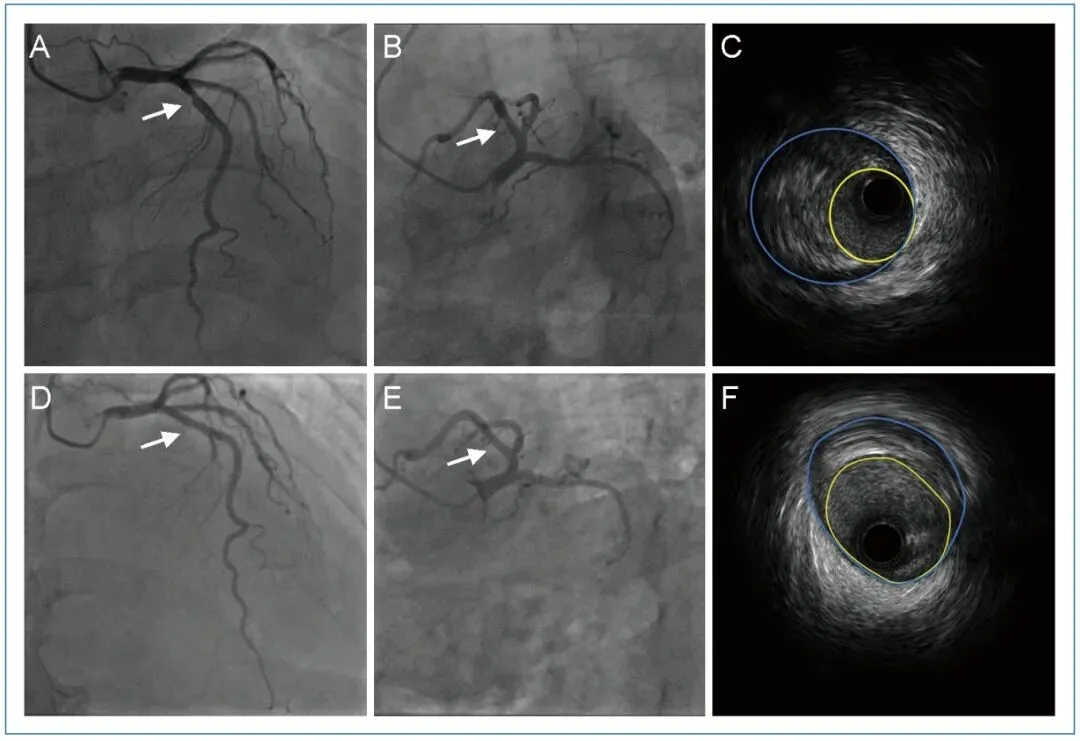

关键检查:入院时 LDL-C 水平为 3.59 mmol/L,心电图(ECG)正常,超声心动图提示主动脉瓣钙化。冠脉造影显示左前降支(LAD)近端狭窄 50%,左回旋支(LCX)、右冠状动脉(RCA)正常;血管内超声(IVUS)显示 LAD 近端存在软性纤维斑块,最小管腔面积(MLA)为 4.31 mm²,外弹力膜(EEM)面积为 14.97 mm²,斑块负荷(PB)达 71%(图1)。

图1. 患者的冠脉造影和血管内超声显示冠状动脉斑块消退

2023 年 6 月,患者因胸部不适再次入院,血压控制良好,ECG 正常,超声心动图提示轻度主动脉反流及主动脉瓣钙化。此时 LDL-C 为 2.03 mmol/L。冠脉造影显示,LAD 近端不规则(较 2017 年明显改善),LCX、RCA 正常。IVUS 显示 LAD 近端为轻度纤维斑块,最小管腔面积(MLA)达 7.48 mm²,外弹力膜(EEM)面积为 13.68 mm²,斑块负荷(PB)降至 45%。出院时,治疗方案中加用依折麦布片。

本案例中,患者经 IVUS 证实其 LAD 斑块负荷从2017年的71% 降至 2023年的45%,MLA 从 4.31 mm² 增至 7.48 mm²。在接受中等强度他汀治疗期间,尽管 LDL-C 水平维持在约 2.6 mmol/L(高于显著消退的常规目标值),但患者仍呈现明显的斑块消退。这一改善可能源于以下几个因素: